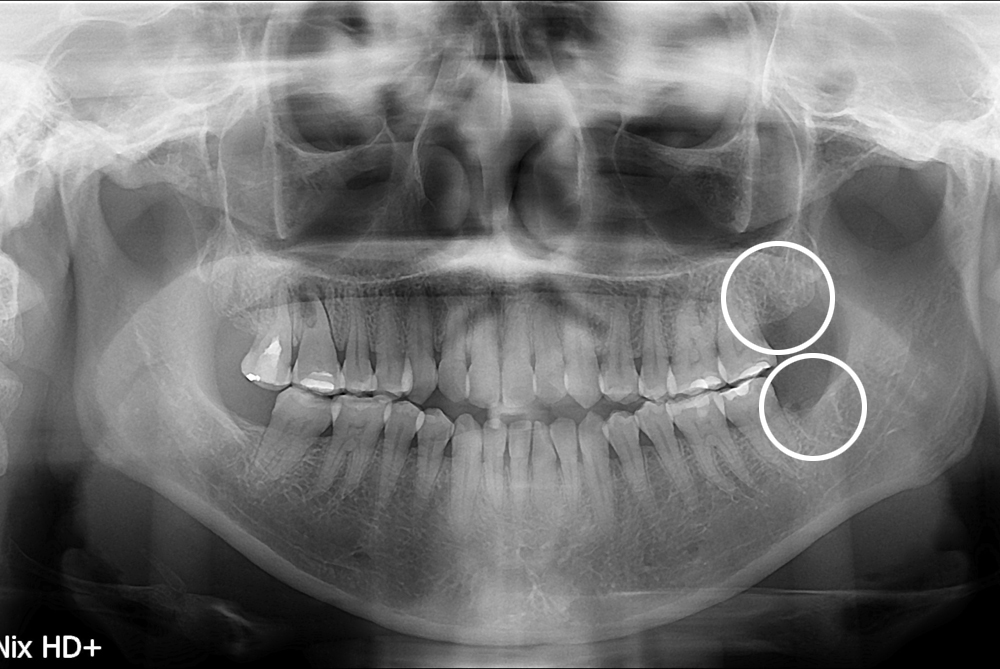

치료사례

세종치과의 진심 어린 치료는 결과로 말합니다.

실제 내원하신 환자분들의 치료 전·후 사례를 확인해보세요.

모든 치료사례 전후사진은 환자분의 동의하에 촬영되었습니다.

모든사진은 동일 환자분의 전후모습을 촬영하였으며, 사진의 밝기조절 외에 임의 수정이 없음을 알려드립니다.